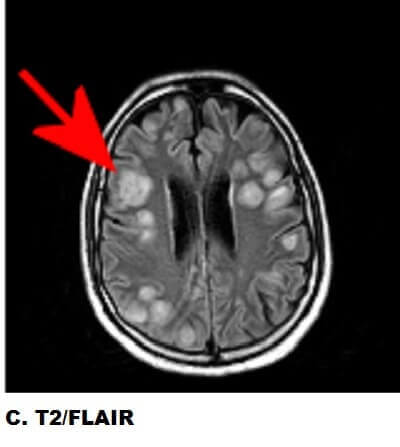

Figure 1: Red arrows. A : Axial susceptibility weighted images demonstrate multifocal regions of decreased signal (increased susceptibility) suggestive of petechial hemorrhage. B : The lesions demonstrate restricted diffusion (ADC signal is also decreased) and are situated at the grey-white junction. C : The lesions demonstrate increased T2/FLAIR signal with relatively little vasogenic edema.

There is an extensive differential for multifocal T2/FlAIR hyperintense lesions in the brain parenchyma including neoplasm (metastasis, lymphoma), infection (abscess, septic emboli), infarct (vasculitis), trauma (diffuse axonal injury) and demyelinating disease (multiple sclerosis). The peripheral distribution at the grey white junction follows regions of greatest blood flow within the brain suggesting a systemic origin like septic emboli and metastasis.

Neoplasms generally incite significant vasogenic edema and lack central restricted diffusion, which suggests an infectious process in this case. Septic emboli are infected embolic debris that originate most commonly from central venous cathethers, thrombophelbitis and endocarditis. Introvenous drug users and immunocompromised patients are predisposed. Multiple cavitary pulmonary lesions can also result from septic emboli.